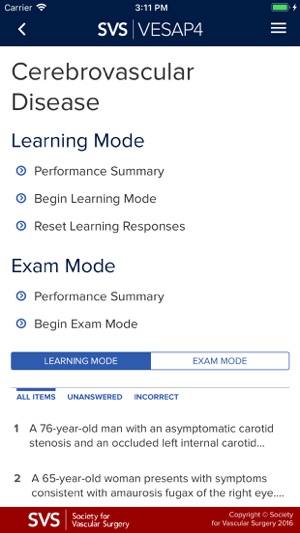

VESAP4 has over 500 questions and includes detailed discussions and references for each question. You may use this product in Learning Mode as often as you like. You will not earn CME credit or MOC self-assessment credit in Learning Mode; however, you will be able to review a rationale for the responses and will access available abstracts in PubMed.

In Learning Mode, you can view the correct answer to each question, the rationale and references. At the end of each session, you may save your answers and return at a later time or you may elect to end the session and view your score. You may use this product in Learning Mode as often as you like and you make take all or part of the exam.

In Exam Mode, you may navigate throughout the question bank, you may take as much time as you like and you can save your answers and return at a later time to complete the exam. In Exam Mode, you will not be able to view the rationale, references or the correct answers.